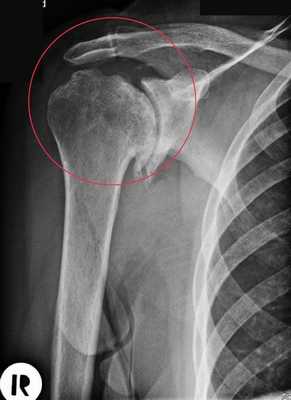

- Рентгенологическое исследование включает рентгенограммы в передне-задней, боковой подмышечной, Y-лопаточной проекциях и в положении внутренней ротации плеча. Рентгенограммы используются как для диагностики (рис. 1), так и для подбора компонентов протеза:

• Особое внимание следует обратить на угол версии суставной впадины лопатки и ее эрозивные изменения на рентгенограмме в подмышечной проекции

• Подмышечная проекция (рис. 1)